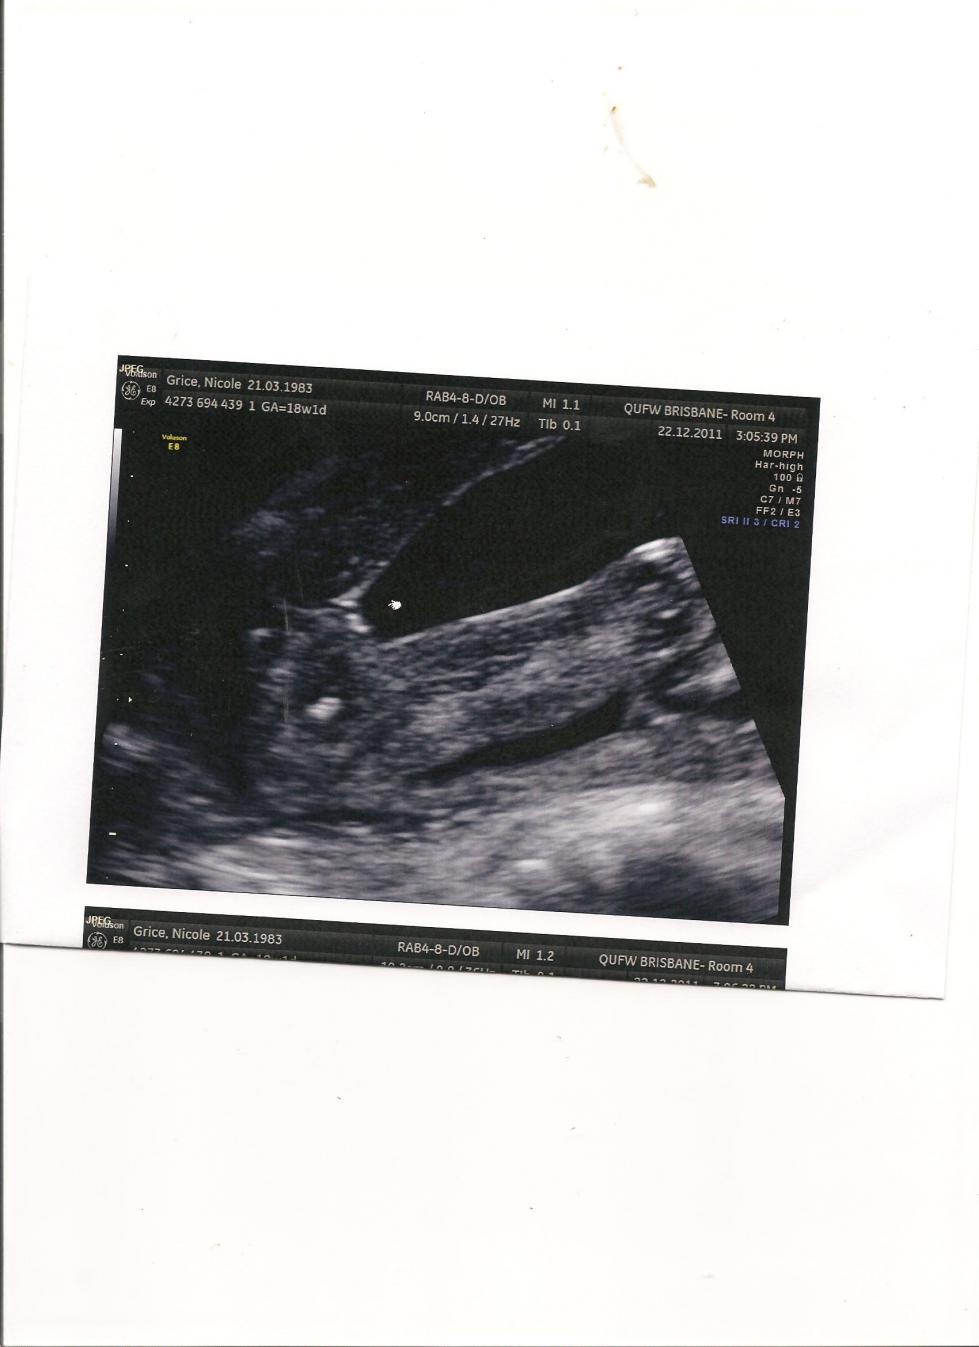

This question has been on my mind since my last gender scans which I had at 16 weeks, and 18 weeksn both confirmed girl with really good girl looking potty shots - I think.

So why do I keep hearing stories about people who were told one gender only to give birth to another or find out in a later ultrasound? in particular girl turns into boy? what causes this to happen? If you have lots of really good potty shots of Girly lines is there the chance that the penis was hiding, hasnt grown at 18 weeks?

here is my 18wk potty shot for reference.Attachment 1044